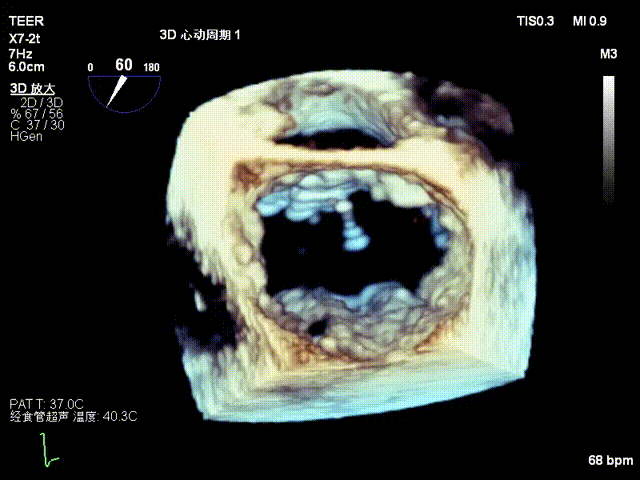

术前影像

左房极小

房间隔增厚

3D